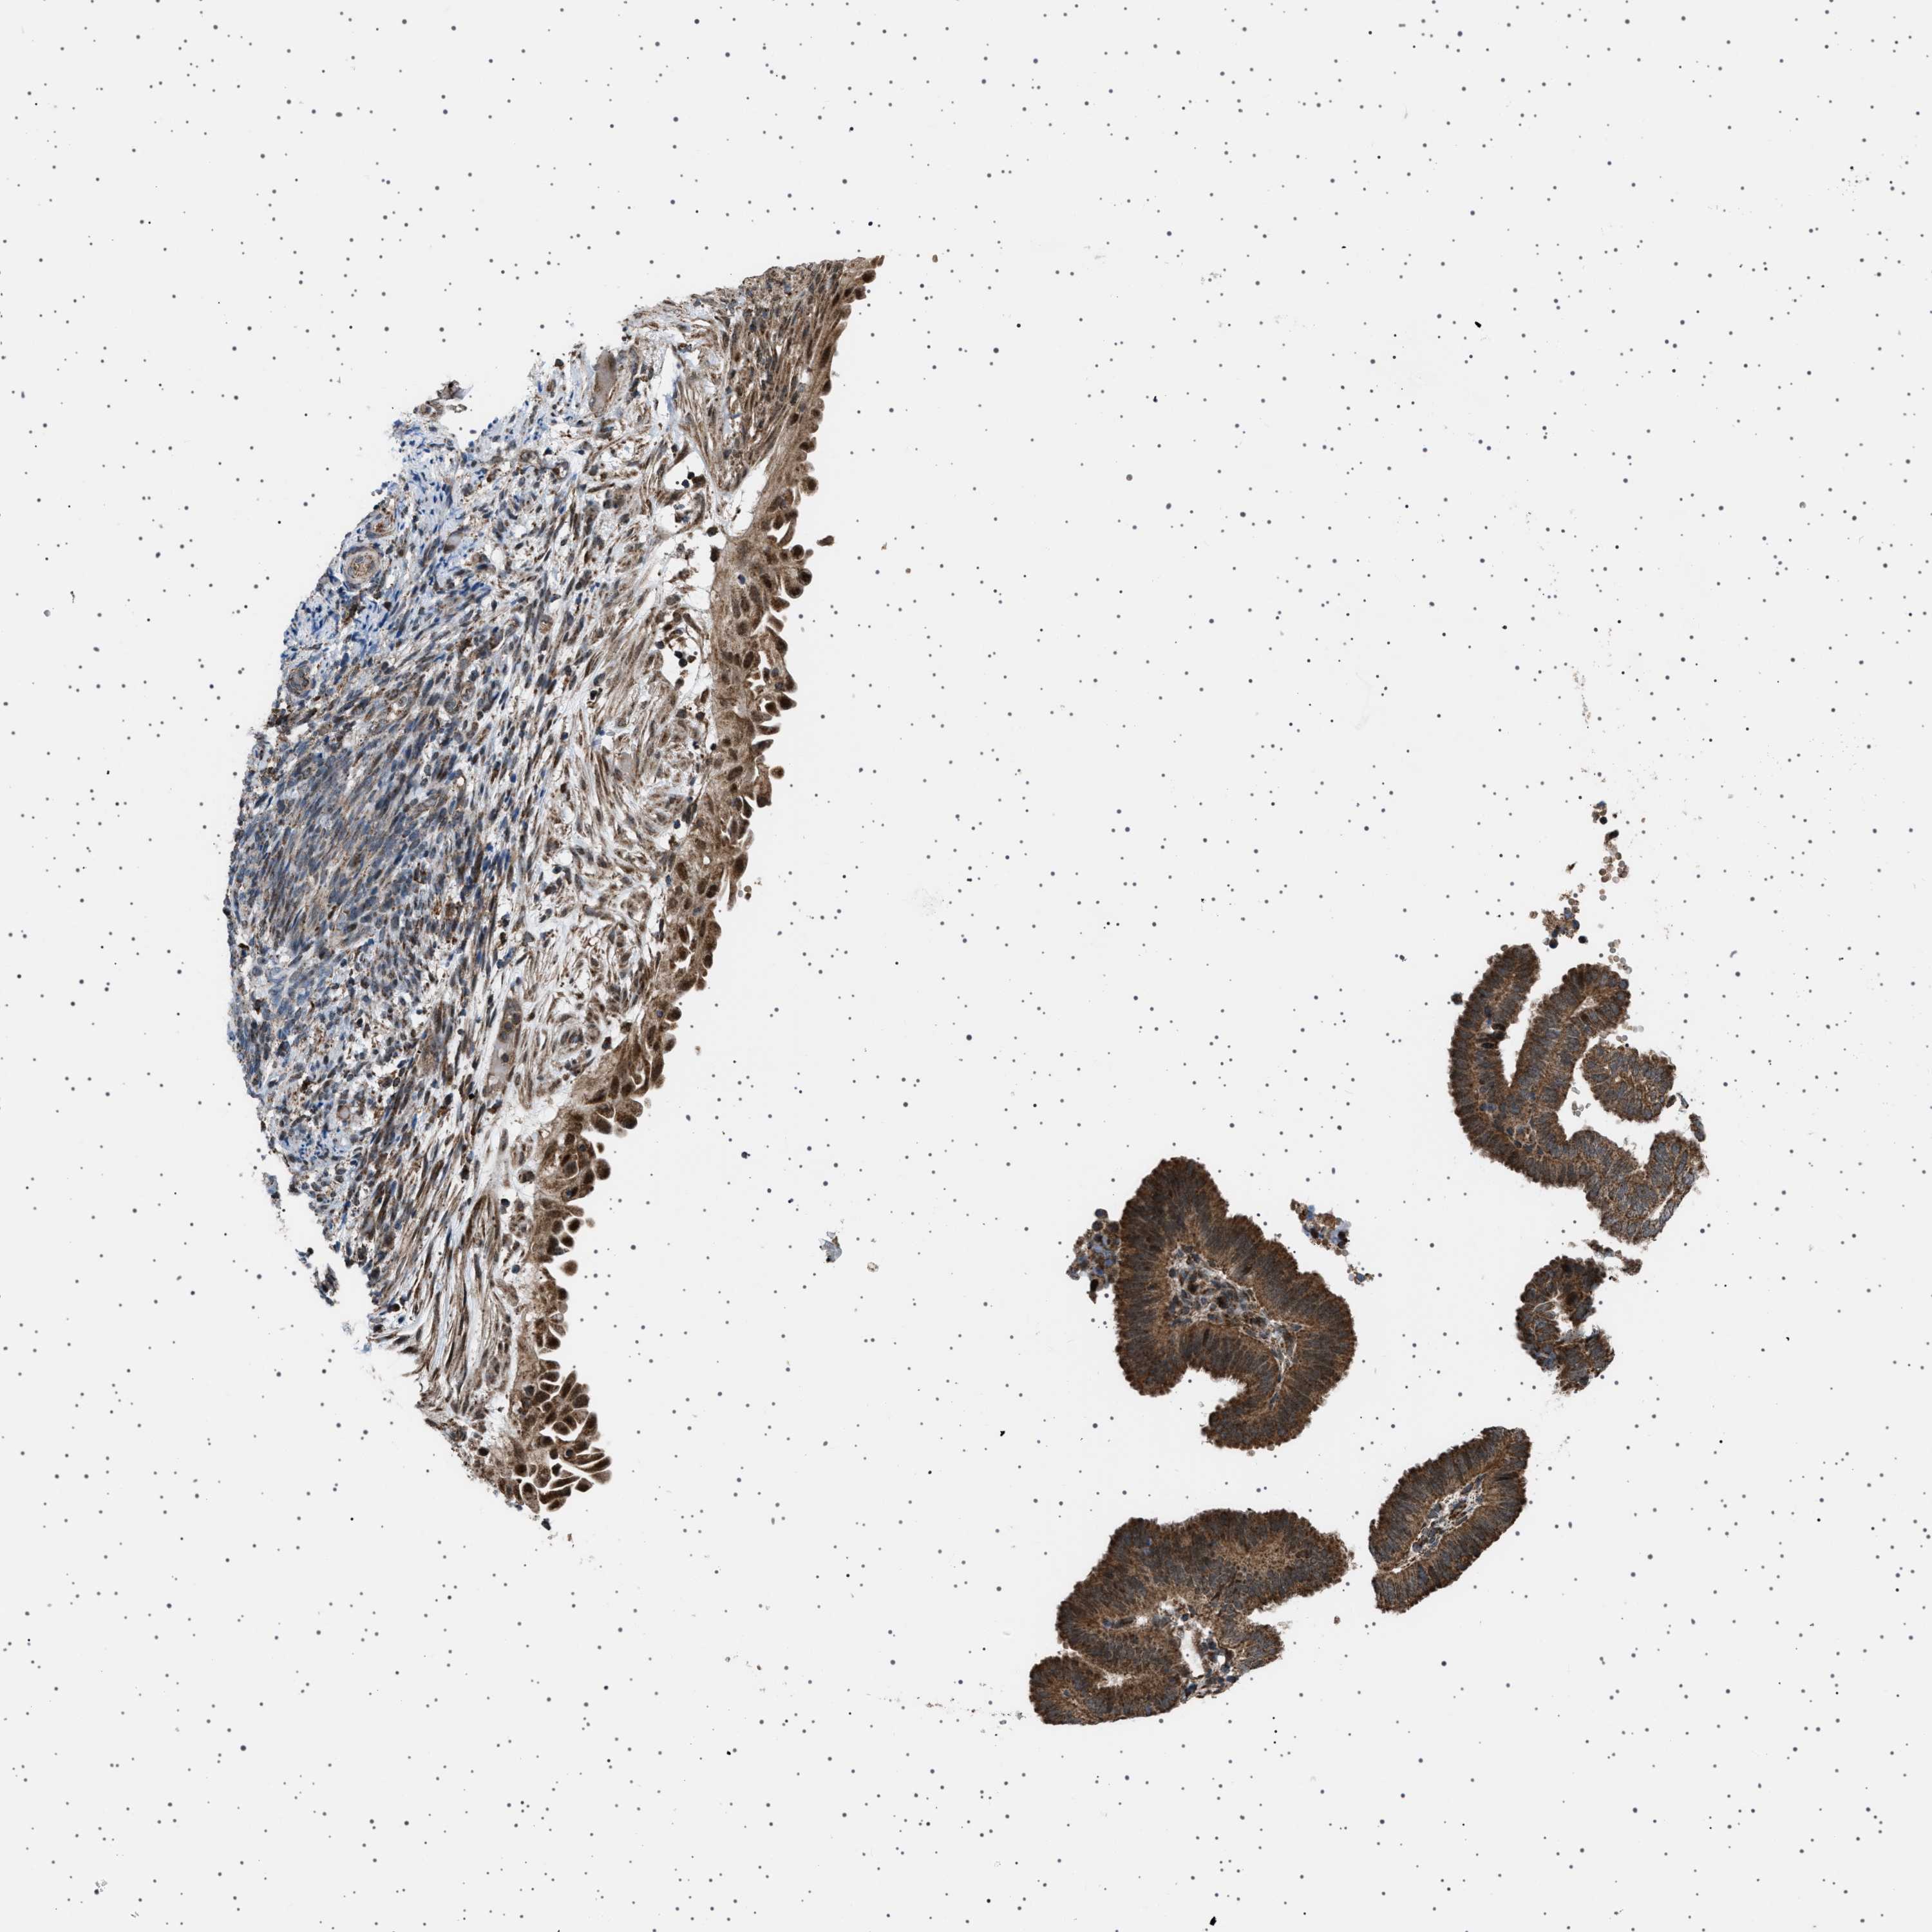

ENDOMETRIAL CANCER - Protein expressioni

A mouse-over function shows sample information and annotation data. Click on an image to view it in a full screen mode. Samples can be filtered based on level of antibody staining by selecting one or several of the following categories: high, medium, low and not detected. The assay and annotation is described here.

Note that samples used for immunohistochemistry by the Human Protein Atlas do not correspond to samples in the TCGA dataset.

Antibody stainingi

Antibody staining in the annotated cell types in the current human tissue is reported as not detected, low, medium, or high, based on conventional immunohistochemistry profiling in selected tissues. This score is based on the combination of the staining intensity and fraction of stained cells.

Each image is clickable and will lead to virtual microscopy that enables deeper exploration of all samples and also displays staining intensity scores, fraction scores and subcellular localization as well as patient and tissue information for each sample.

Antibody HPA017214

Staining

High

Medium

Low

Not detected

Intensity

Strong

Moderate

Weak

Negative

Quantity

>75%

75%-25%

<25%

None

Location

Nuclear

Cytoplasmic/membranous

Cytoplasmic/membranous,nuclear

Adenocarcinoma, NOS